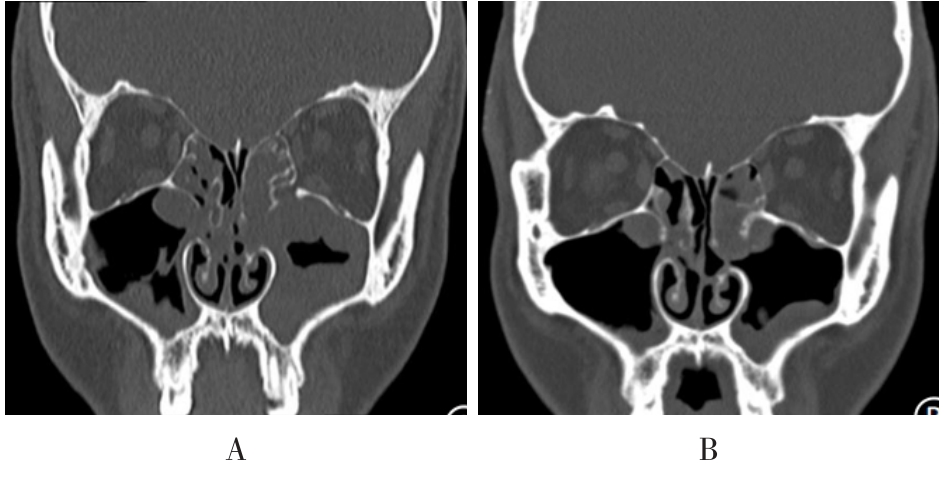

• 术前规范化药物治疗对鼻内镜下慢性鼻窦炎伴鼻息肉患者术后鼻黏膜重塑的影响

摘要:目的 探讨术前规范化药物治疗对鼻内镜下慢性鼻窦炎(CRS)伴鼻息肉(CRSwNP)患者术后鼻黏膜重塑的影响。方法 选取2022年1月-2023年6月该院收治的CRSwNP患者80例,根据随机数表法将患者分为观察组(n = 40)和对照组(n = 40),对照组给予功能性鼻内镜手术治疗,观察组在对照组的基础上给予术前规范化药物综合治疗。比较两组患者鼻腔黏液纤毛清除功能、鼻功能和鼻黏膜重塑变化;采用广义估计方程(GEE)模型,分析其改善情况;采用多元线性回归模型,分析其与各评分之间的关系;采用双重差分模型,分析治疗效果。结果 两组患者组内不同时点(治疗前、治疗后3个月和治疗后6个月)的糖精清除时间、鼻黏液纤毛清除率、黏液纤毛清除速率、鼻腔容积(NCV)、鼻腔最小横截面积(NMCA)、最小横截面积距前鼻孔距离(DCAN)、嗜酸性粒细胞(EOS)、转化生长因子β1(TGF-β1)和血管内皮细胞生长因子(VEGF)水平比较,差异均有统计学意义(F = 124.36,P = 0.000;F = 113.58,P = 0.000;F = 98.67,P = 0.000;F = 87.37,P = 0.000;F = 107.26,P = 0.000;F = 77.45,P = 0.000;F = 3.80,P = 0.008;F = 2.56,P = 0.012;F = 2.13,P = 0.015);观察组治疗后3和6个月糖精清除时间较对照组短,鼻黏液纤毛清除率较对照组高,黏液纤毛清除速率较对照组快,NCV和NMCA较对照组大,DCAN较对照组短,EOS、TGF-β1和VEGF水平较对照组低,差异均有统计学意义(F = 44.36,P = 0.000;F = 38.23,P = 0.000;F = 30.44,P = 0.000;F = 27.33,P = 0.000;F = 36.11,P = 0.000;F = 22.00,P = 0.000;F = 2.44,P = 0.014;F = 1.89,P = 0.017;F = 1.75,P = 0.021);两组患者糖精清除时间、鼻黏液纤毛清除率、黏液纤毛清除速率、NCV、NMCA、DCAN、EOS、TGF-β1和VEGF水平变化趋势比较,差异均有统计学意义(F = 18.33,P = 0.000;F = 15.78,P = 0.000;F = 13.00,P = 0.000;F = 8.17,P = 0.002;F = 10.23,P = 0.000;F = 4.34,P = 0.004;F = 2.89,P = 0.013;F = 1.67,P = 0.022;F = 1.43,P = 0.031)。GEE分析结果显示,观察组鼻黏液纤毛清除率、黏液纤毛清除速率、NMCA、NCV、DCAN和糖精清除时间的改善情况明显优于对照组,差异均有统计学意义(P < 0.05);治疗后6个月,两组患者Lund-Kennedy评分、Lund-Mackay评分和鼻腔鼻窦结局测试-20(SNOT-20)评分明显低于术前,且观察组明显低于对照组,差异均有统计学意义(P < 0.05);多元线性回归模型分析结果显示,糖精清除时间、DCAN、EOS、TGF-β1、VEGF水平、鼻黏液纤毛清除率、黏液纤毛清除速率、NCV和NMCA与Lund-Kennedy评分、Lund-Mackay评分和SNOT-20量表评分密切相关(P < 0.05)。双重差分模型结果显示,观察组Lund-Kennedy评分、Lund-Mackay评分和SNOT-20量表评分的改善情况明显优于对照组。观察组总有效率为92.50%,明显高于对照组的75.00%,差异均有统计学意义(P < 0.05)。结论 在鼻内镜术前采用规范化药物治疗,可以有效地促进CRSwNP患者鼻黏膜修复,抑制术后鼻腔重塑,且疗效较好,值得临床推广应用。